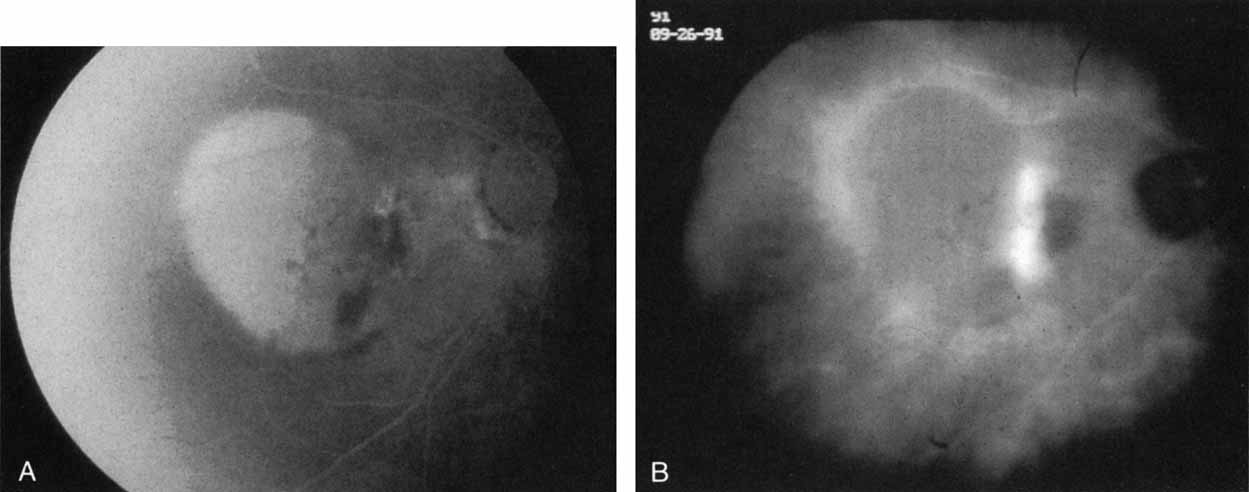

Harada disease, an inflammatory condition often affecting both eyes in young patients, is typified on fluorescein angiography by multiple focal areas of hypofluorescence early in the study, followed by late confluent leakage in the later phases (Fig. 17A, 17B, and 17C). With ICG angiography, multiple focal hypofluorescent spots are seen in the early phases, many more than were noted on the fluorescein study64,68 (Fig. 17D). The process extends further than the clinically or angiographically involved areas. The spots vary in size and density but appear to be well circumscribed. In the later phases of the ICG study, there is generalized hypofluorescence, with masking of the background choroidal fluorescence by the neurosensory detachment (Fig. 17E). This masking effect covers a large area, with inferior round margins confirming the gravitating nature of the neurosensory elevation. In addition, focal hyperfluorescent spots can be seen, possibly representing sites of active chorioretinal leakage or inflammation. In one patient, steroid therapy resulted in a marked resolution of clinical findings within 1 week.68 Repeat ICG angiography revealed a marked resolution of the hypofluorescent lesions as well as the hyperfluorescent spots. New areas of hypofluorescence did appear, the significance of which remains undetermined (Fig. 17E).

Fig. 17 Clinical photograph of a patient with Harada disease demonstrating multiple serous elevations of the retinal pigment epithelium with an overlying shallow neurosensory detachment. B. Early-phase fluorescein angiogram demonstrating hypofluorescent spots at the site of localized inflammation. C. Late-phase fluorescein study demonstrating hyperfluorescence in a confluent nature in the central macula. D. Early-phase indocyanine green (ICG) study demonstrating hypofluorescent spots in the central macular region. Note that the lesions are more numerous and more widely distributed than noted on clinical or fluorescein angiographic examination. E. Late-phase ICG study demonstrating extensive areas of confluent hypofluorescence. Note the curvilinear and gravitating nature of these hypofluorescent lesions, which are believed to represent blocked fluorescence from the shallow neurosensory detachment. Focal hyperfluorescent spots are noted within this region, which may represent areas of more active inflammation.